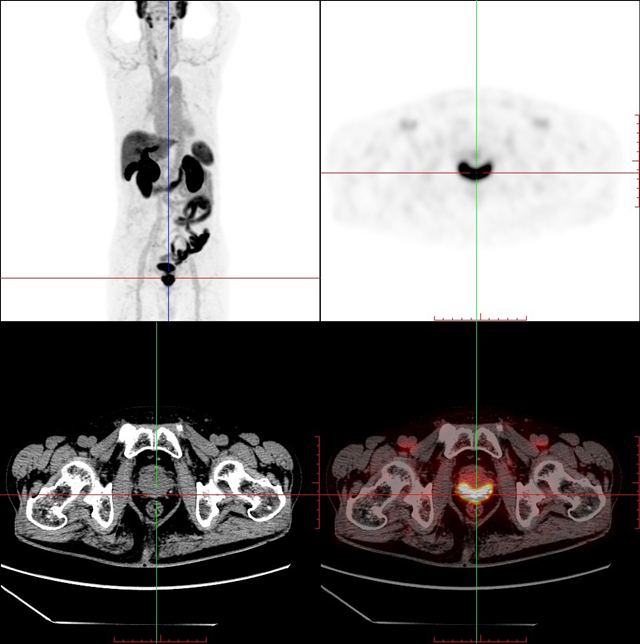

兰大二院完成省内首例前列腺癌特异性PSMA PET-CT显像

9月5日,兰大二院核医学团队在泌尿外科和联勤保障部队940医院甘肃省放射药物重点实验室的大力支持下,成功完成了甘肃省首例前列腺癌特异性18F-PSMA-1007 PET-CT(前列腺特异性膜抗原正电子发射型计算机断层)显像。此项技术填补了甘肃省空白,在国内仅有少数几家医院尝试开展,为前列腺癌患者带来了福音。

PSMA,前列腺特异性膜抗原是一种II型跨膜糖蛋白,在90%以上的前列腺癌细胞中高特异性表达,是前列腺癌诊断特异性靶点。18F-PSMA-1007 PET-CT显像作为一种无创的全身性影像检查,在诊断原发前列腺癌的同时,可对患者进行分期及危险度分层以及复发的监测,实现一站式的影像学评估,为临床医师提供最全面最精准的临床分期,对指导治疗意义重大。

18F-PSMA-1007 PET-CT显像